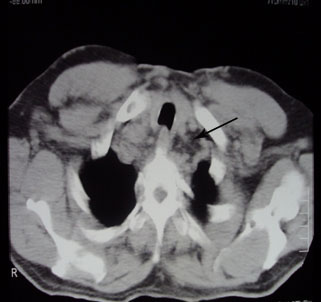

possibility of Idiopathic Fibrosing Mediastinitis. CT scan

chest shows fibrosis of mediastinum (black arrow) distended

azygos vein (white arrow), Right sided aorta (white arrow head) MRI chest